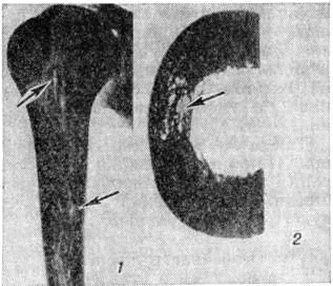

В костном мозге, по данным трепанобиопсии, на первых стадиях заболевания скопления бластных клеток являются очаговыми, в достаточном количестве обнаруживаются элементы деятельного костного мозга. Нередко наблюдаются острые расстройства кровообращения, участки гипоплазии, могут обнаруживаться некрозы. Прогрессирование заболевания характеризуется увеличением числа и размеров лейкозных разрастаний, их слиянием, а затем диффузной инфильтрацией ткани костного мозга. Количество нормальных кроветворных клеток заметно уменьшается. Часто имеется инфильтрация надкостницы, возможно распространение процесса в окружающие мягкие ткани. Развитие лейкозных разрастаний сопровождается выраженным рассасыванием костной ткани, преимущественно по типу гладкой резорбции. Очень редко в этом процессе принимают участие остеокласты. Вследствие частичного, а местами и полного рассасывания костных балок происходит значительное расширение костномозговых полостей, истончение, а в некоторых участках разрушение кортикального слоя. В раннем детском возрасте резкие изменения наблюдаются в зоне энхондрального окостенения. При острых Лейкозы редко отмечается очаговое новообразование атипичной костной ткани, богатой остеоидом, разрастание фиброзной ткани. Наряду с мелкими фокусами некроза иногда возникают обширные инфарктообразные коагуляционные некрозы, определяемые макроскопически в виде жёлто-белых сухих участков; в окружности наблюдаются кровоизлияния, возможно скопление макрофагов (рисунок 1). В области лейкозных разрастаний нередко обнаруживается истончение и частичный распад ретикулярных волокон. Описаны наблюдения с очаговым или диффузным миелофиброзом, который чаще выявляется при миелобластном Лейкозы. В таких случаях при пункции обычно не удаётся получить костный мозг и для установления диагноза необходимо исследование материала трепанобиопсии.

Лейкозная инфильтрация ткани селезёнки и лимфатических, узлов сопровождается уменьшением размеров (рисунок 2) и числа фолликулов вплоть до полного их исчезновения. В селезёнке часто наблюдается инфильтрация трабекул с разволокнением стенок трабекулярных сосудов, с деформацией и сужением их просвета, имеются поля кровоизлияний. В лимфатических, узлах вначале возникают очаговые инфильтраты, которые по мере прогрессирования болезни увеличиваются в размерах, и поражение становится диффузным.